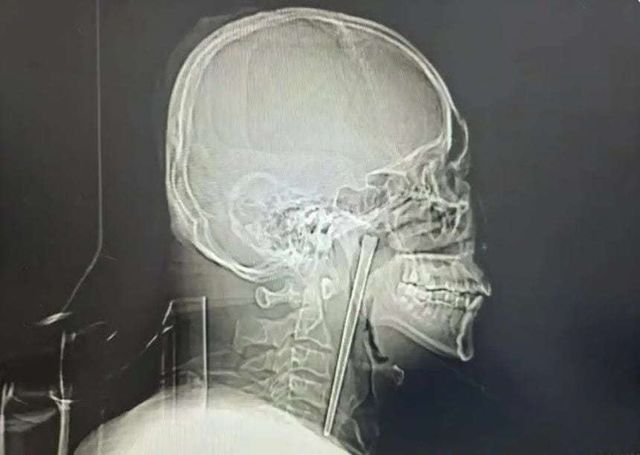

사진=바이두

중국에서 한 남성이 길이 12㎝에 달하는 금속 젓가락이 목에 박힌 채로 8년간 생활하다가 뒤늦게 수술로 제거한 사실이 알려졌다.

19일(현지 시간) 사우스차이나모닝포스트(SCMP)에 따르면 중국 랴오닝성 다롄에 거주하는 왕 씨는 최근 다롄시 중심병원에서 목에 박혀 있던 젓가락을 제거하는 수술을 받았다.

보도에 따르면 왕 씨는 8년 전 음주 상태에서 식사를 하다 실수로 금속 젓가락을 삼켰다. 당시 왕 씨는 통증은 있었지만 호흡에는 문제가 없었고, 의료진이 목을 절개해 젓가락을 제거하는 수술을 권유했지만 이를 거부했다.

이후 왕 씨는 간헐적으로 이물감을 느꼈지만, 이를 음주로 인한 숙취 등 일시적인 증상이라 여기며 별다른 치료를 받지 않았다. 그러다 몇 주 전부터 아침마다 통증이 심해지고, 음식물을 삼킬 때 고통이 커지자 다시 병원을 찾았다.

진료를 맡은 의료진은 검사 결과 그의 연구개(입천장 뒤쪽 부위)에 금속 젓가락이 박혀 있는 것을 확인했다. 다행히 주변 점막이나 장기에는 큰 손상이 없었고, 성대 기능도 정상적으로 유지된 상태였다.

의료진은 환자가 목 절개를 거부했던 점을 고려해 입을 통한 최소 침습 수술을 진행했고, 길이 12㎝의 젓가락을 성공적으로 제거했다. 수술은 소량의 출혈만 발생한 채 비교적 순조롭게 마무리됐으며, 왕 씨는 회복 후 며칠 만에 퇴원한 것으로 전해졌다.송치훈 기자 sch53@donga.com